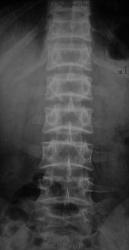

Ребенок 8 лет поступил в детское травматологическое отделение с болями в спине. На мой взгляд позвонки не нормальные. Изменены по типу рыбьих. может это вариант нормы или какая то система. Дистрофический процесс? Какие ваши мнения. и при каких состояниях, если это патология, мы можем видеть данные изменения. Буду рад полезным ссылкам)

прошу прощенья. ребенку 14 лет.

Рыбьи позвонки описывает Майкова-Строганова как результат остеопоротических изменений.(Кости и суставы в рентгеновском изображении. Туловище). БМЭ и Рейнберг такие позвонки относят к врожденным деформациям.

И еще:"Рыбьи позвонки — позвонки с двояковогнутыми краниальной и каудальной пластинками. Характерны для несовершенного остеогенеза, некоторых эндокринных спондилопатий, гемобластозов, хронического отравления солями тяжелых металлов." Э.В. Ульрих, А.Ю.Мушкин. Вертебрология в терминах, цифрах и рисунках, Спб, 2005

На счет "выпирания"дисков для меня сомнительно. При ф-х пробах все ок. Про смещения позвонков тоже недостоверно-смещение должно быть смещением(для меня). Про spina bifida - вполне согласен. Про анамнез уточню в понедельник, также про спорт и тд. Но мой главный вопрос - это двояковогнутые позвонки - норма или нет . и где предел нормы. За мнения спасибо.

Если это ребенок, то скорее всего рыбьи позвонки результат дисплазии

Нормальным может быть "слегка вогнутая" поверхность тел позвонков в боковой проекции. Но не "столь вогнутая", как в данном случае. Тем более, что к 14 годам все уже почти как у взрослых. Вывод однозначен - не норма.